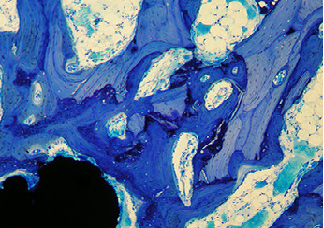

天狼星染色vs股骨病理分析

番红快绿